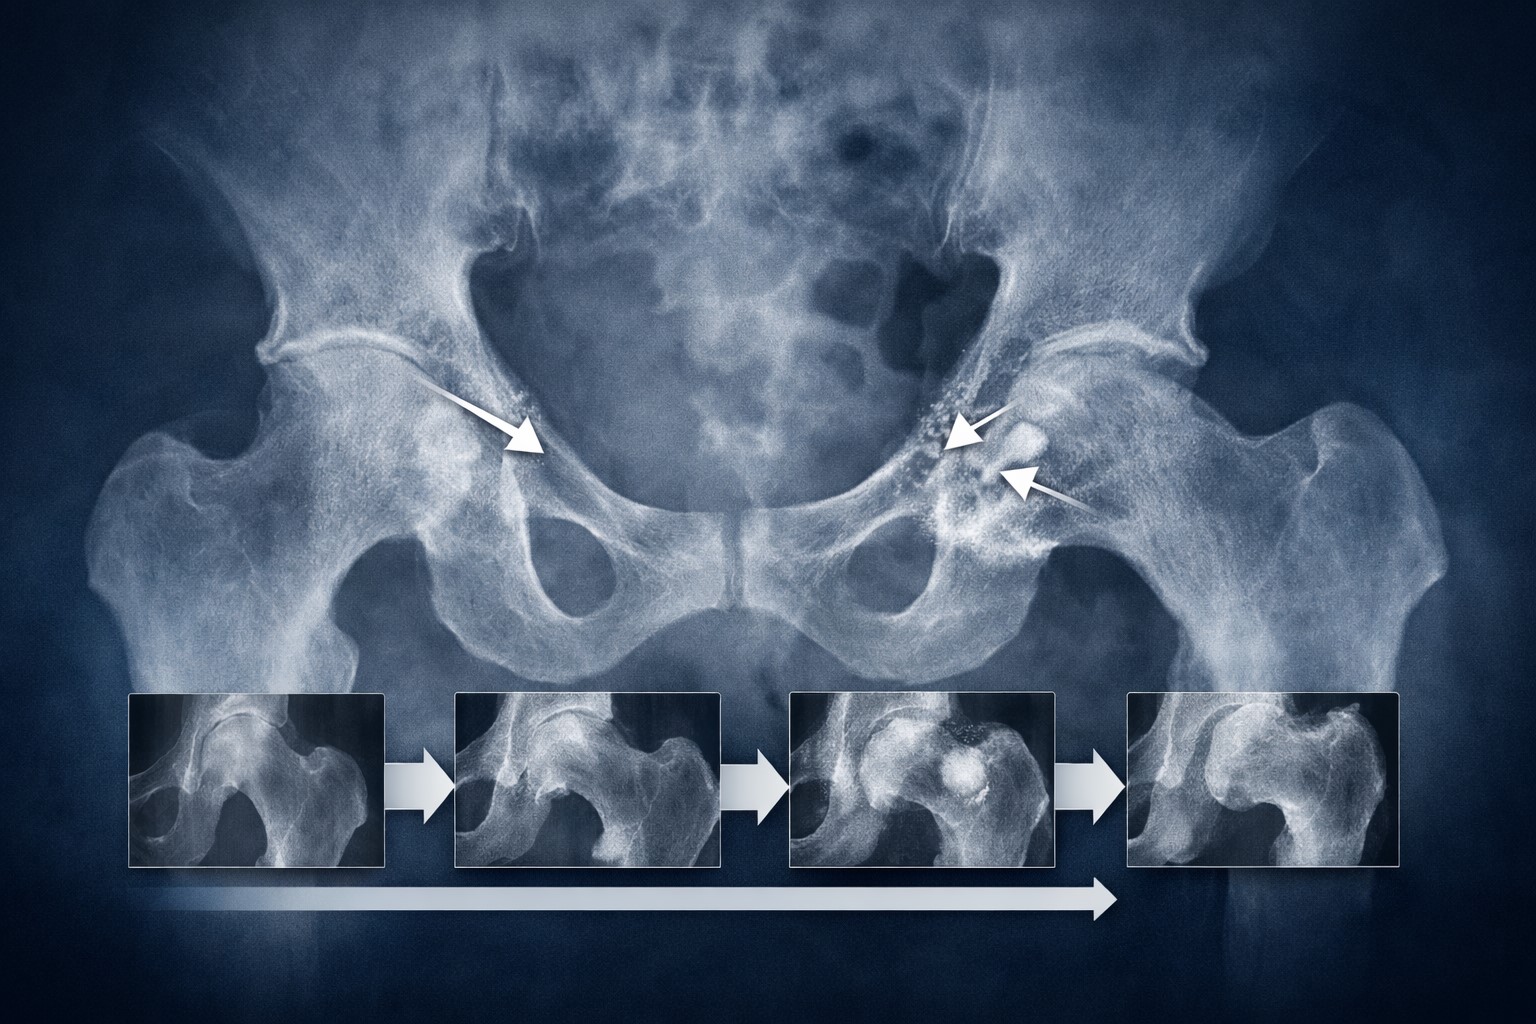

③ 進行期に見られる代表的なレントゲン所見

### 骨棘(こつきょく)の形成

解説「進行すると、骨の縁に“骨棘”と呼ばれる突起が見られることがあると言われています。これは体が関節を安定させようとする反応と考えられています。」

### 骨硬化・骨嚢胞の変化

解説「レントゲンで骨が白く濃く見える状態は“骨硬化”と呼ばれます。また、黒く抜けたように見える部分は“骨嚢胞”と表現されることがあります。」

これらは中〜後期に見られる傾向があるそうです。

### 末期像の特徴

関節裂隙がほぼ消失し、骨の変形が明確になるケースもあります。ただし、ここでも症状の感じ方には個人差がある点が強調されています。

### 代表的な分類の考え方

Tönnis分類やKellgren–Lawrence分類では、

関節裂隙の変化

骨棘の有無

骨硬化や変形

などを総合的に評価します。